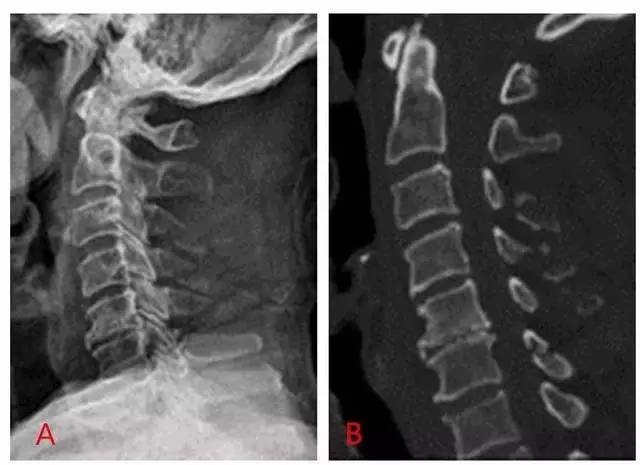

图为铲土者骨折(C3~C5)的平片(A)及 CT 扫描(B)(来源:Radiopaedia)